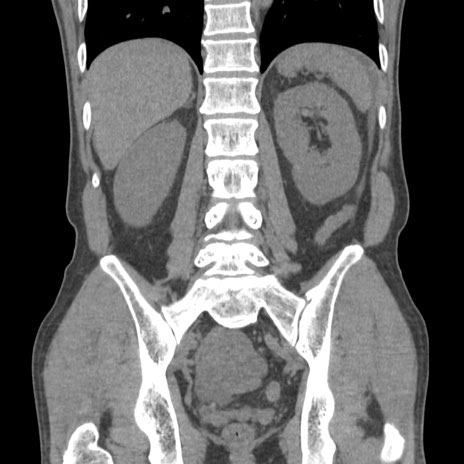

症例56 CT(冠状断像)

脂肪ウインドウ